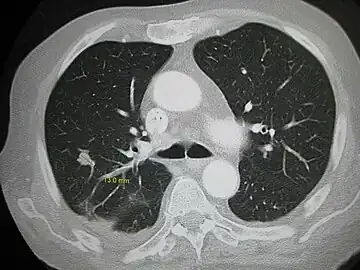

![]() | |

| Illustration showing hematogenous metastasis | |